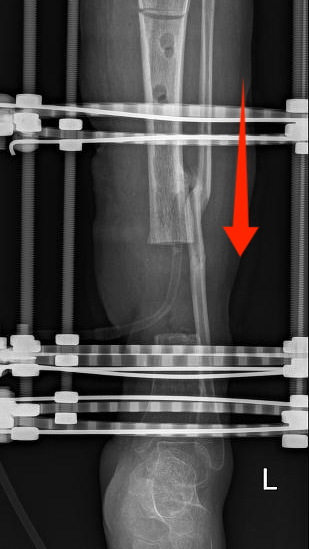

多年来,贵州航天医院各科室紧跟医学前沿,不断强技术、补短板,大力开展新技术、新项目,完成了许多高精尖、高难度、本地区“首例”的技术,填补了医院医疗技术空白,满足了群众日益增长的医疗需求。 贵州航天医院骨科率先在遵义地区开展骨搬移技术,截至目前,已治愈慢性骨髓炎、感染性骨不连、骨缺损、脉管炎、糖尿病足患者200余例,糖尿病足治疗保肢率达到98%。 本期,我们将为大家带来骨科特色技术——骨搬移技术(Ilizarov)。 案例分享 一名59岁的患者,身患糖尿病12年,在来我院3个月前出现了右脚溃烂的症状,来院就诊时,患者的右脚十分红肿,右脚脚趾坏死,伤口处不断流出黑红色脓液,情况十分严重。在接诊到患者时,骨科专家团队高度重视,立刻为患者完善了CT血管造影(CTA)等相关检查,诊断为:2型糖尿病,糖尿病周围血管病变,右糖尿病足。 术 前 考虑到患者情况比较严重,为最大限度保证患者肢体完整,科室专家团队进行了严格的讨论评估,为患者制定了骨搬移技术治疗方案,在征得患者及其家属的同意后,成功通过搬移骨块为患者进行治疗,促进患者病变肢体血管再生。 胫骨横向骨搬移外架固定 清除感染病灶 术后调节外架,通过搬移骨块 促进患肢血管再生 患者在术后三周前来换药,观察到感染得到进一步控制;术后六周复查,患者病变处已愈合,进行CT血管造影(CTA)后可明显观察到足部血管再生。 术后3周 术后6周愈合 CT血管造影见足部血管再生 糖尿病患者全身与局部的问题互为影响,形成恶性循环,糖尿病足溃疡创面迁延不愈,常见干性坏疽、湿性坏疽、趾坏死、深且大的溃疡以及骨髓炎等症状,还可导致脓毒血症,以往为保全生命,患者被迫选择一次或多次截肢。骨搬移技术的发展进步,能在血糖有效控制、局部有效清创下,有效促进患肢微血管再生,改善患肢血供,达到糖尿病足更快治疗康复的目的,并能根据病变情况最大限度的保障患者肢体完整。 什么是骨搬移技术 骨搬移技术是通过使用专用的骨外固定器固定骨段,每天缓慢牵拉,在牵拉搬移过程中,骨段尾部形成新骨及新的软组织,从而修复骨骼缺损及软组织缺损。是治疗大段骨缺损、骨不连、骨感染、肢体畸形的金标准方法,也用于治疗脉管炎、糖尿病足等肢体缺血性疾病。 骨感染缺损 切除感染段 搬移骨段 新骨形成 骨感染根治愈合 骨搬移技术原理 生物组织在持续、稳定、缓慢牵拉下,能刺激细胞分裂、组织再生,骨外固定技术运用该原理,通过持续缓慢调节外固定器形成牵拉张力,促进牵引成骨与相邻组织再生,如神经、血管、肌肉、皮肤等再生,达到治疗大段骨缺损、肢体缺血如糖尿病足等疾病的目的。 骨搬移技术优势 (一)除治疗骨缺损、骨不连外,有更广的适用范围,利用组织再生、血管再生等特性,能大量运用于肢体畸形的矫形、糖尿病足等的治疗。 (二)治疗效果确切,重建肢体外型和功能,极大降低截肢率和残疾率。 (三)明显提高了患者生活质量,极大减轻其家庭及社会负担。 肢体畸形的矫形 慢性骨髓炎 骨段切除 术后1年 濒临截肢的脉管炎术后6周 难愈创面术后3周 贵州航天医院骨科 专家团队 赵学平 骨科主任 主任医师 临床擅长:从事骨科临床工作30余年,对骨科常见疾病的诊治具有丰富的临床经验。 世界中医药联合会脊柱康复专业委员会常务理事,中华中医药学会整脊分会常务委员,中国中西医结合学会骨伤科分会肢体矫形功能重建与康复专家委员会常务委员,中国研究性医院学会骨科创新与转换专业委员会关节外科学组保髋工作委员会常委,中国康复技术转化及发展促进会骨外科与康复技术转化专业委员会常务委员,泛珠三角区域运动医学联盟(PPRD-SMA)理事会常务理事,中国研究型医院学会运动医学专业委员会委员,贵州省中医药学会整脊分会副主任委员,贵州省中西医结合学会银质针专业委员会副主任委员,贵州省康复医学会骨与关节专业委员会常务委员,贵州省人民医院骨科专科联盟常务理事,贵州省康复医学会骨内科专业委员会常务委员,中华医学会贵州省骨科学会委员,贵州省康复医学会脊柱脊髓专业委员会常务委员,贵州省运动医学分会委员,贵州省康复医学会骨与软组织肿瘤专业委员会委员,遵义市医学会创伤分会副主任委员,贵州省康复医学会骨内科专业委员会遵义地区分会常务委员,遵义市医疗事故鉴定、伤残鉴定、工伤鉴定、司法鉴定专家。 长期从事骨科临床研究及教学工作,在国家级、省部级杂志发表论文20余篇,SCI论文2篇,参与主编骨科专著2部,主持省部级科研项目2项,参与指导省部级、市级科研项目6项。 陈明勇 骨科副主任 副主任医师 临床擅长:从事创伤骨科工作约20年,对骨缺损、骨不连、骨肿瘤、肢体畸形等的肢体矫形重建及功能重建,慢性化脓性骨髓炎的根治治疗、糖尿病足的保肢治疗、快速康复理念(ERAS)下的老年骨折的诊治,四肢复杂骨折的诊治,四肢骨折等微创手术治疗具有丰富的临床经验。 2004年毕业于遵义医学院临床专业,曾在中国人民解放军总医院、广西医科大学第一附属医院、上海第六人民医院骨科进修。中国中西医结合学会骨伤科专业委员会横向骨搬移治疗糖尿病足及微血管网再生学组首届委员,遵义市医学会创伤分会常务委员。 瞿 辉 骨科 副主任医师 临床擅长:对骨科的常见病、关节外科、脊柱外科及运动医学疾病的诊治具有丰富的临床经验,熟练掌握骨科手术操作技术。 毕业于遵义医学院临床医学系,2005年前往广州中山大学第一附院骨显微医学部进修学习,2011年前往成都华西医院进修学习,并多次在省内外学习骨科相关知识,是中华医学会骨科分会会员。 赵兴东 骨科 主任医师 临床擅长:擅长骨科的常见病及各种创伤、四肢骨折创伤修复、骨感染、手足疾病的诊治和手足体表畸形的矫形整复,熟练掌握骨科四肢骨病及创伤的手术操作技术,尤其在四肢关节复杂性损伤、手足外伤、组织缺损创面、难治创面的皮瓣修复方面及平足、高弓足矫形方面及四肢慢性疼痛诊治、康复方面具有丰富的临床经验。 硕士研究生,毕业于遵义医学院临床外科系,2015年前往山东省立医院手足外科进修学习;遵义市医学分会创伤分会第一、二届委员,遵义市手外科医学会第二委届员会常务委员;在省级及省级以上期刊发表文章9篇,参编著作2部,参与主持并完成市级课题1项,参与市级课题2项、省级课题1项。 张俊凯 骨科 副主任医师 临床擅长:从事骨科临床工作28年,对创伤骨折、骨感染、骨缺损、骨不连等外科诊治,四肢骨折的微创手术治疗,四肢复杂骨折(如关节内粉碎性骨折、多发骨折等)的损伤控制及手术治疗等具有丰富的临床经验。 1995年毕业于遵义医学院临床专业,2009年前往复旦大学附属医院骨科进修1年。 卢懿明 骨科 副主任医师 临床擅长:从事骨科工作18年,对创伤骨折、四肢骨折的微创手术治疗、四肢复杂骨折(如关节内粉碎性骨折、多发骨折等)的损伤控制及手术治疗,尤其是髋部骨折的PFNA等微创技术,踝关节骨折、膝关节周围骨折的Mipo微创技术等具有丰富的临床经验,开展了4项新技术,发明6项新型专利技术。 2005年毕业于遵义医学院临床专业,2017年,前往南方医科大学第三附属医院骨科进修半年,回院后运用Mipo技术对骨干骨折及干骺端骨折的治疗技术,同时积极开展骨盆骨折、髋臼骨折腹直肌外侧切口的应用;发表了多篇专业论文,经常参与省内外学术交流会授课,获得医院荣誉称号多个。 邬夏荣 骨科 副主任医师 临床擅长:从事骨科工作16年,对四肢复杂骨折、骨肿瘤的诊治,尤其是足踝创伤、慢性踝关节损伤、平足症等诊疗具有丰富的临床经验。 2006年毕业于遵义医科大学临床医学专业,曾在陆军军医大学西南医院进修学习,发表多篇骨科学术论文。 余德怀 骨科 副主任医师 临床擅长:从事骨科工作10余年,对运动医学、骨关节、脊柱外科常见病、多发病的诊治具有丰富的临床经验。 硕士研究生,2011年毕业于遵义医学院临床医学专业,曾前往遵义医科大学附属医院运动医学专业进修学习;是贵州省医学会运动医学分会青年委员,西部关节镜联盟委员;发表多篇骨科学术论文。 冯 乾 骨科 副主任医师 临床擅长:从事骨科工作近20年,熟练掌握骨科多发病及常见病的诊治,尤其对脊柱退变性疾病的诊断及治疗具有丰富的临床经验,主要研究脊柱微创相关治疗方式,能熟练开展椎间孔镜及VBE。 曾前往北京大学第三医院进修学习疼痛及椎间孔镜、首都医科大学友谊医院专业进修脊柱内镜;是贵州省康复医学会第三届脊柱脊髓专业委员会委员;发明专利3项、发表脊柱外科专业论文多篇。 张艳金 骨科 副主任医师 临床擅长:从事骨外科工作16年,对复合伤、多发伤的救治、四肢骨干骨折、关节周围骨折、骨肿瘤、骨髓炎等诊治具有丰富的临床经验。 中共党员,硕士研究生,2006年本科毕业于山西医科大学第二临床医学院,2011年研究生毕业于北京军区总医院;在“老年COPD患者合并髋部骨折的诊治”国际合作课题组研究两年,在老年髋部骨折的诊治方面具有丰富的经验,并发表论文6篇;承担遵义市级课题1项;承担遵义医科大学的临床教学工作,获得遵义医科大学优秀带教老师荣誉。编撰有《骨科疾病诊疗精粹》一书,开展2项新技术,编撰地方规范《务川自治县创伤骨科常见疾病诊疗规范》一书。 赵小锋 骨科 副主任医师 临床擅长:从事骨科临床工作11年,对骨科常见病、多发病诊疗有较为丰富的临床经验,擅长脊柱相关疾病诊断及治疗,尤其是颈、腰、腿疼痛疾病诊断及治疗,擅长胸腰椎骨折微创经皮穿刺内固定术、经皮穿刺椎体成形术、经皮穿刺脊柱内镜下腰椎间盘摘除术、单纯开创腰椎间盘摘除术、腰椎滑脱复位椎间植骨椎融合内固定术、腰椎管狭窄减压融合内固定术及人工髋、膝关节置换术等。 2012年毕业于遵义医学院外科学专业硕士研究生,2019年参加“遵义市115医学人才精英计划”于上海交通大学第一附属医院培训学习,2023年于北京大学第三人民医院脊柱外科进修学习,曾获得遵义市优秀医师荣誉称号。 遵义市手外科第一届委员,遵义市医学会创伤分会第一届委员,遵义市医学会创伤分会第二届委员,贵州省康复医学会第三届脊柱脊髓专业会委员,遵义市医学会烧伤与整形外科学分会委员,发表论文5篇,其中国家级核心期刊1篇,SCI论文1篇,主持市级课题1项并结题,参与市级课题2项。 贵州航天医院骨科简介 基本情况 贵州航天医院(原3417医院)骨科组建于1968年,前身是以创伤和断肢(断指)再植闻名于世的上海市第六人民医院骨科,中国断肢(断指)再植的奠基者、中科院院士陈仲伟等著名专家、学者多次莅临科室指导医疗、教,是贵州省最早拥有专业骨科技术科室之一,在70年代开展了贵州省首例断肢(断指)再植手术。组建50余年来,诊治患者已逾百万,挽救了无数的伤病员,成为了保障遵义地区人民群众健康的重要支撑。 经过几代人的不懈努力,今天的骨科,已由创伤骨科发展至骨病、骨肿瘤、骨结核等领域,现有脊柱外科、关节外科、四肢创伤、手足外科四个亚专科,成为了集医疗、教学、科研于一体的综合学科,是贵州省临床重点专科、遵义市临床重点专科、遵义市骨科临床医学中心、遵义市基层骨科专科联盟理事长单位。 科室目前开放床位110张,共有医护人员50余人,副高级以上专家18人,硕士研究生15人。拥有一流骨科医疗设备多台,每年不定期选派优秀技术骨干到全国各大知名医学院校进修、学习、参观、交流,并邀请国内、国外知名专家教授来院进行交流、指导,通过不断引进国内外先进的诊疗技术,科室医疗技术水平稳步提升,为广大人民群众提供了优质的医疗服务。 专科特色 骨一科 (一)骨缺损、骨不连的肢体与功能重建 胫骨横向骨搬移技术治疗糖尿病足: (二)慢性骨髓炎的根治治疗 (三)肢体缺血性疾病如糖尿病足、脉管炎的保肢治疗 (四)皮瓣修复 (五)复杂创伤的治疗 (六)老年髋部骨折及小儿骨折快速手术 老年髋部骨折: 骨二科 (一)胸腰椎骨折微创经皮椎弓根螺钉固定术 (二)老年性骨质疏松性患者腰椎滑脱脊柱内固定术(骨水泥螺钉) (三)V形双通道脊柱内镜技术(VBE)腰椎融合术治疗腰椎退行性疾病 (四)老年性骨质疏松性骨折(PVP/PKP)术 (五)人工髋关节置换术 (六)双侧股骨头坏死人工全髋关节置换 (七)右侧全髋置换术后假体周围骨折翻修 (八)人工膝关节置换术 (九)人工膝关节假体松动翻修 (十)关节镜技术 传统手术切口 关节镜技术切口 诊疗范围 骨一科 1.四肢创伤、矫形。 2.手、足踝外科。 骨二科